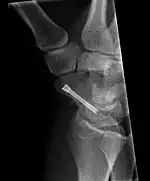

The scaphoid can be slow to heal because of the limited circulation to the bone. Fractures of the scaphoid must be recognized and treated quickly, as prompt treatment by immobilization or surgical fixation increases the likelihood of the bone healing in anatomic alignment, thus avoiding mal-union or non-union.[6] Delays may compromise healing. Failure of the fracture to heal ("non-union") will lead to post-traumatic osteoarthritis of the carpus.[1]: 189 One reason for this is because of the "tenuous" blood supply to the proximal segment.[3] Even rapidly immobilized fractures may require surgical treatment, including use of a headless compression screw such as the Herbert screw to bind the two halves together.

Healing of the fracture with a non-anatomic deformity (frequently, a volar flexed "humpback") can also lead to post-traumatic arthritis. Non-unions can result in loss of blood supply to the proximal pole, which can result in avascular necrosis of the proximal segment.

Scaphoid fractures may be difficult to diagnose via plain x-ray. A repeat x-ray may be required at a later date, as might cross-sectional imaging via MRI or CT scan.[6]